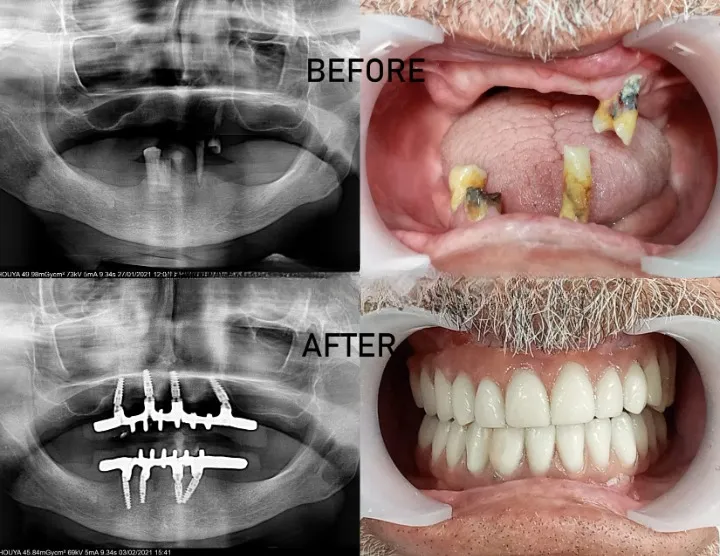

Chirurgie Régénératrice

Reconstruction de l'os et regeneraiton tissulaire grâce aux biomatériaux et membranes. Redonner du support aux dents déchaussées.